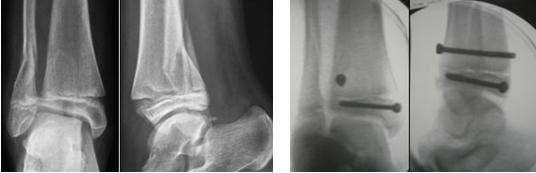

Anche nel trattamento dei distacchi epifisari tibiali distali il trattamento elettivo è conservativo. E’ necessaria tuttavia un riduzione anatomica in modo da ripristinare la continuità della placca cartilaginea ed evitare la formazione di ponti ossei di epifisiodesi che comporterebbero successiva dismetria o deformità.

In caso di riduzione imperfetta o perdita di riduzione in gesso si ricorre al trattamento chirurgico.

In tutti i casi (sia nel trattamento conservativo che chirurgico) è necessaria la contenzione in apparecchio gessato per 30 giorni. Successivamente in base alla evoluzione dei processi riparativi può essere avviata la mobilizzazione articolare evitando il carico per almeno 3 mesi. Torna su